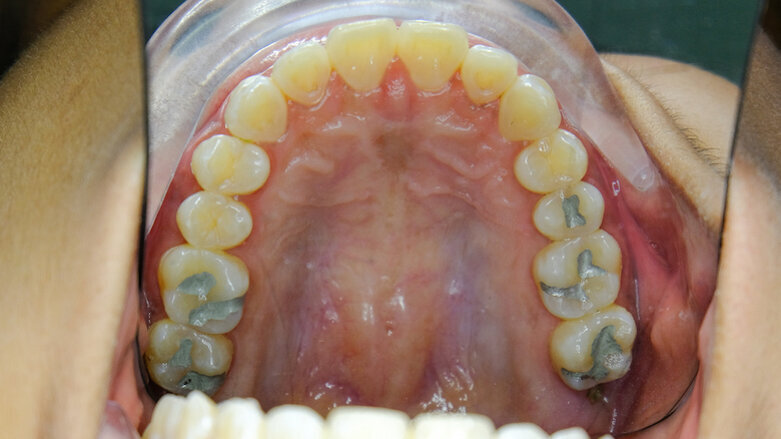

SAN JUAN, Puerto Rico/SPRING, Texas, U.S.: Mercury in dental amalgam is a hidden source of global mercury pollution, resulting from factors such as the illegal diversion of dental mercury into the artisanal and small-scale gold mining industry, crematoria emissions from the deceased and sewage sludge that is sold to farmers. These significant mercury sources result in air, water and food contamination that consequently have a negative impact on human health. The aim of a recent study was to investigate and report on all of the various pathways of mercury in dental amalgam into the environment.

According to the United Nations Environment Programme, dental amalgam represents over 20% of the global mercury used in products. The Minamata Convention on Mercury is now in force, 110 countries of the 128 signatories having ratified the treaty. Countries are now working on implementation for treaty compliance.

The environmental impact that is caused by dental amalgam has been discussed within the text of the treaty, and factors such as sewage sludge, cremation, burial, human waste, and artisanal and small-scale mining are mentioned. However, there has been little research on the topic. According to the authors of the study, they believe that it is the first paper to address all of the pathways through which mercury from dental amalgam enters the environment as a cradle-to-grave deadly pollutant. They also stated that significant mercury pollution from cremation is growing owing to various factors. Cremation is less expensive than burial and is favored because of population density and lack of burial space. This increase in cremation is happening globally.